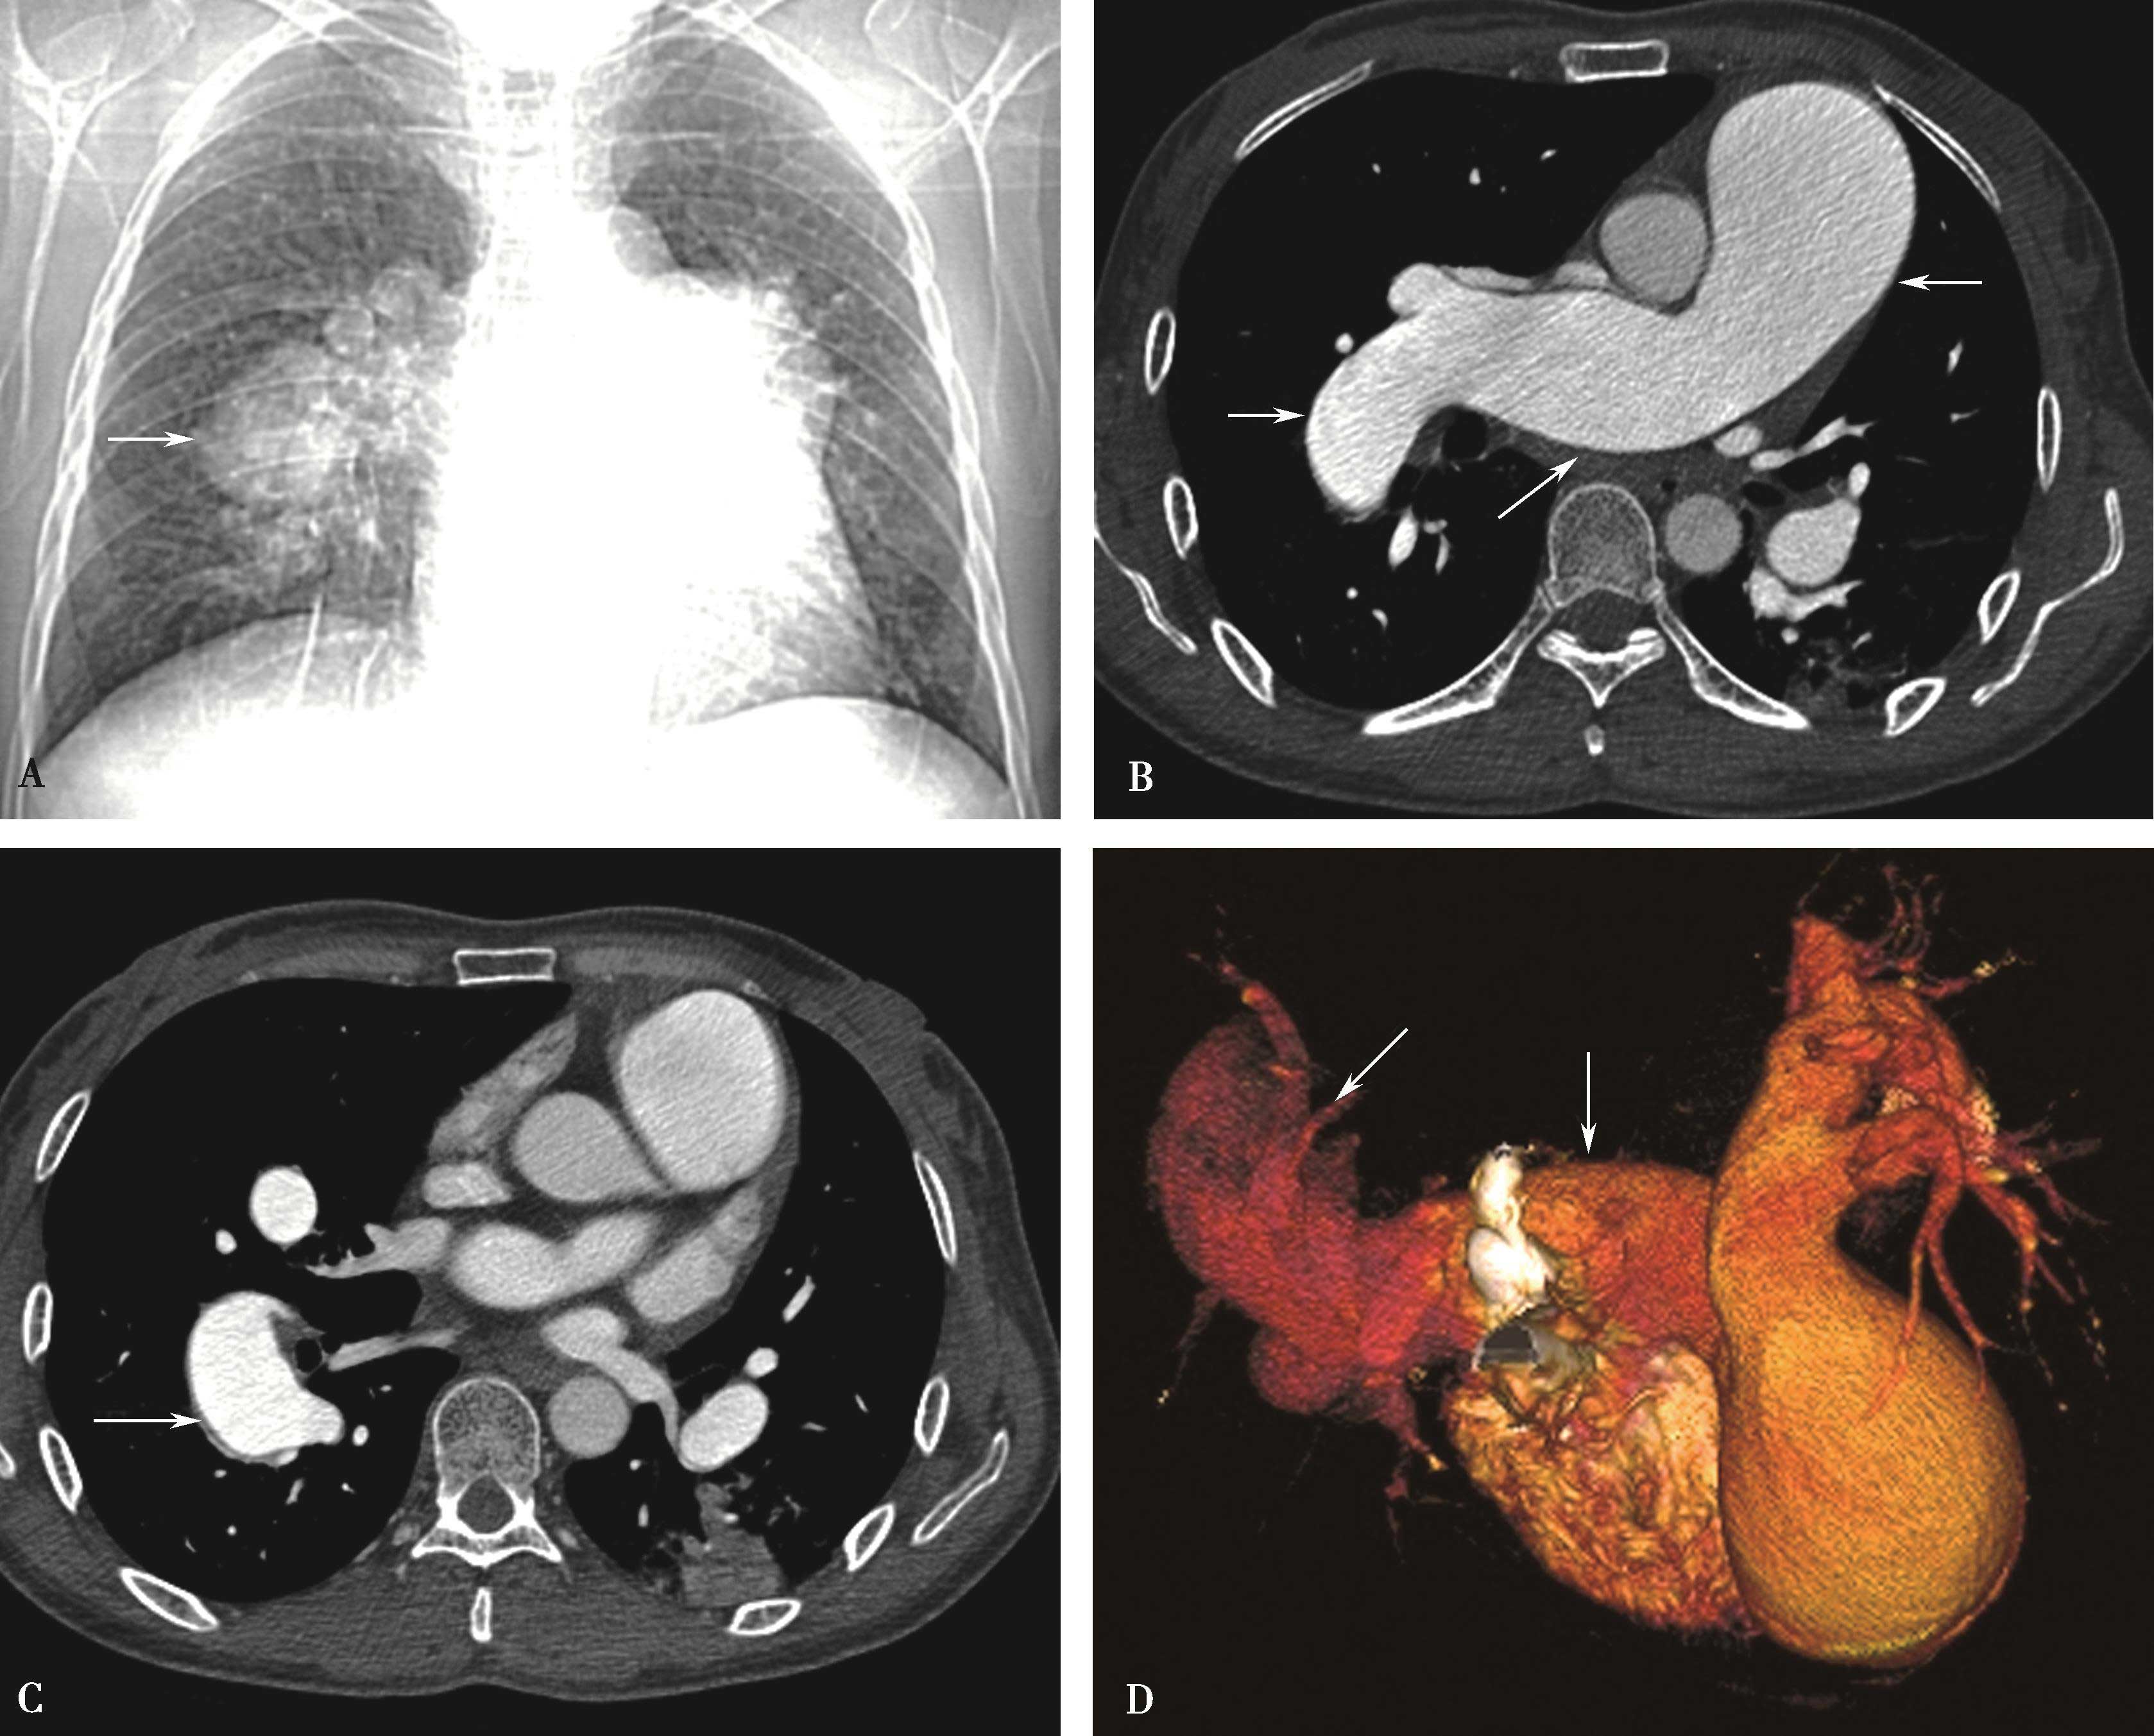

图8-5-5 男,28岁,反复口腔及生殖器溃疡5年,白塞病,肺动脉瘤

A.胸部X线片,示左右肺动脉瘤(↑);B.横断图像,左、右下肺动脉动脉瘤形成,附壁血栓形成(↑);C.多层重组(冠状位)示右下肺动脉动脉瘤合并附壁血栓(↑);D.多层重组(左前斜位)示左下肺动脉瘤合并附壁血栓形成(↑)。CT诊断:左右肺动脉瘤,附壁血栓形成,病变性质白塞病

白塞病(Behcet disease,BD)是以血管炎为主要病理基础的慢性多系统疾病。该病与HLA-B51强关联,感染或异常自身免疫应答(尤其是细胞免疫)参与发病。临床上以口腔溃疡、生殖器溃疡、眼炎及皮肤损害为突出表现,又称为口-眼-生殖器综合征。白塞病累及心血管特点为淋巴细胞、浆细胞浸润,弹力纤维破坏,侵犯心脏瓣膜、心内膜炎,累及主动脉瓣、二尖瓣造成瓣叶脱垂、关闭不全;累及房间隔瘤并发血栓形成。累及血管病变特点:①动脉炎呈现淋巴细胞、浆细胞浸润,弹力纤维破坏;动脉瘤形成-真性、假性,游走性、多发性、重复性为其特点,占48%。②静脉炎;急性血栓性静脉炎,占20%;③肺动脉炎:主肺动脉及叶-段动脉分支为该病动脉最易受累的部位,多为动脉瘤形成。

白塞病是肺动脉瘤形成的最常见原因,动脉瘤常伴原位血栓形成。

2)肺动脉叶段分支瘤样扩张,真性或假性动脉瘤形成,腔内不同程度附壁血栓(图8-5-5)。